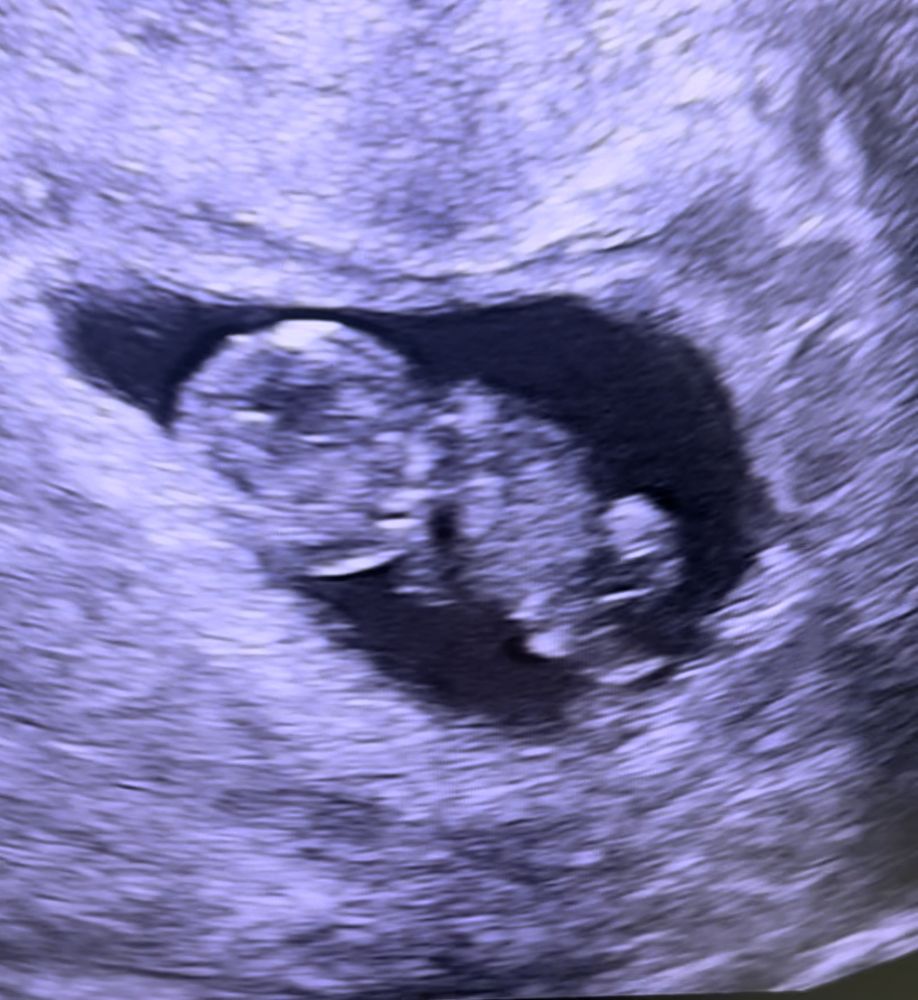

У Вас хороший ракурс) со спины. У меня вот инопланетянин 👾 Изображение

25.06.2024

Какая милота 😍 а какой ктр?)

Ксения , спасибо 🥰 ктр 14,1 мм 😇